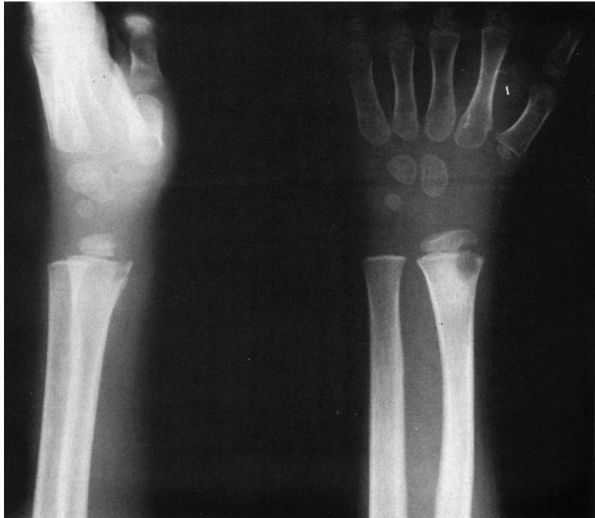

FIGURE 5-10.

Radiographs of an 8-year-old girl with chronic multifocal osteomyelitis who had a longer than 2-year history of multiple sites of bone pain. (A) AP radiograph of the right wrist demonstrating bone destruction of the metaphysis, physis, and epiphysis. (B) AP radiograph of the left wrist demonstrating bone destruction in the metaphysis with periosteal reactive bone. (C) Radiographs of the left ankle demonstrating metaphyseal and physeal destruction of the distal fibula with periosteal reactive bone. |

reaction and are generally located in the metaphyses of the long bones

are seen radiographically (Figure 5-10). The

medial end of the clavicle seems to be the bone that is most frequently

involved, followed by the distal tibia and then the distal femur.

infectious agent is thought to cause these lesions. The histology of

these lesions is typical of osteomyelitis; however, the agent

responsible has not as yet been identified with certainty. The

treatment is symptomatic. The natural history of this disease usually

involves spontaneous resolution of the lesions and the clinical signs

and symptoms, which may take anywhere from 1 to 15 years.